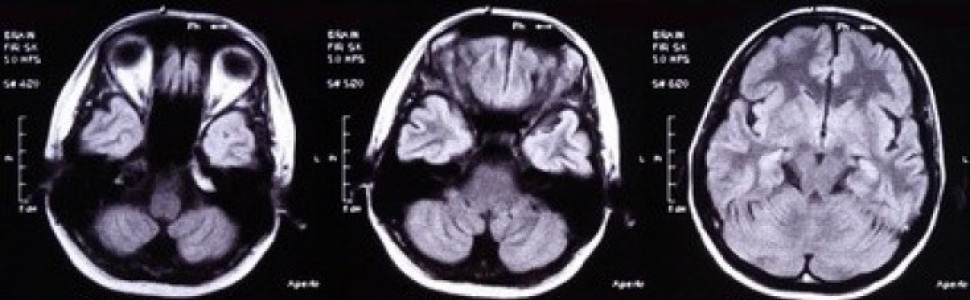

Oprócz oznaczeń laboratoryjnych w diagnostyce płynotoków korzysta się z badań obrazowych. Zdjęcia rentgenowskie wykonywane w różnych płaszczyznach same w sobie nie są w stanie pokazać przetoki, ale mogą dostarczyć przesłanek do podejrzewania uszkodzenia opony twardej w postaci widocznych złamań i odmy śródczaszkowej. Obecność odmy śródczaszkowej wykrywa się u 20% pacjentów z płynotokiem i w 75% ma ona etiologię urazową [6]. Istotnych informacji dotyczących patologii kości czaszki dostarcza badanie tomografii komputerowej (TK) wysokiej rozdzielczości, które jest uznawane za złoty standard

diagnostyczny. Wykonane w oknie kostnym obrazuje podstawę czaszki, pokazuje szczeliny złamań oraz ubytki kostne. Wykazanie w badaniu TK przemieszczenia niektórych struktur kostnych, np. grzebienia koguciego, świadczy wprost o patologii leżącej u podstawy płynotoku – w tym przypadku uszkodzeniu blaszki sitowej kości sitowej. Badanie przy użyciu rezonansu magnetycznego (MRI) – pomimo oczywistych ograniczeń w obrazowaniu struktur kostnych – również stanowi skuteczne narzędzie w identyfikacji przetok. Szczególnie badanie cysternograficzne w sekwencji T2 z supresją tkanki tłuszczowej może pokazać większe przetoki z czułością i swoistością odpowiednio na poziomie 87 i 57% [7]. Dodatkowo drobne modyfikacje procedury badania, np. w postaci umieszczenia pacjenta w pozycji nasilającej płynotok, krótko przed badaniem zwiększa możliwości wykrycia przetoki [8]. W przypadku gdy wykonanie badania MRI jest przeciwwskazane lub nie uwidoczniło miejsca przetoki, korzystać można również z cysternografii TK oraz cysternografii radioizotopowej. Badania cysternograficzne wymagają podawania środka do przestrzeni podpajęczynówkowej, co niesie ze sobą minimalne ryzyko infekcji, zapaleń aseptycznych oraz dyskomfortu dla pacjenta. Jak wykazały liczne badania, zaletą cysternografii TK z użyciem joheksolu lub metryzamidu jest zdolność do wykazania najmniejszych ubytków kostno-oponowych [9, 10]. Badanie cysternografii radioizotopowej zostało zapoczątkowane w 1964 roku przez DiChiro [11]. Do najczęściej stosowanych u ludzi znaczników należy 99m-Tc-DTPA. Badanie może opierać się o dolędźwiowe, podpajęczynówkowe podanie znacznika, a następnie zapis obrazu za pomocą gamma-kamery, która pokazuje obecność znacznika w jamach nosa i zatokach lub oznaczenie radioaktywności tamponów umieszczonych w miejscu spodziewanego płynotoku. Metoda ta, choć skuteczna i według części autorów w korelacji z innymi badaniami dająca 100% pewność lokalizacji przetoki [12], ma również pewne wady. Nie daje się bowiem umiejscowić źródła płynotoku wizualnie, a na dokładność wyniku ma istotny wpływ długość przeprowadzanego badania. Aktywne i wysokociśnieniowe płynotoki można wykryć już w ciągu 0,5-2 godzin. Dla wykrycia dyskretnych przetok trzeba wydłużyć badanie nawet do 48 godz. [13]. Do otrzymania fałszywie dodatnich wyników może przyczynić się zjawisko wchłaniania izotopów do krwiobiegu i następnie ich wydzielania przez błonę śluzową nosa i zatok. Opisano również aktywny mechanizm transportu znaczników z płynu mózgowo-rdzeniowego poprzez nerwy węchowe i blaszkę sitową do nosa i gardła [14]. Inną przydatną techniką, stosowaną również śródoperacyjnie, jest podawanie drogą punkcji lędźwiowej barwnika, np. fluoresceiny lub indygokarminy. Do jamy nosowej lub przewodu słuchowego zewnętrznego zakłada się tampony, które usuwa się po kilku godzinach. Podczas badania pacjent pochylony jest ku przodowi. Tampony w przypadku fluoresceiny ogląda się następnie w ultrafiolecie. Alternatywą do zakładania tamponów jest użycie endoskopu ze specjalnym filtrem umożliwiającym w czasie rzeczywistym wykrycie fluoresceiny i lokalizację przetoki. Liczne doniesienia o toksyczności fluoresceiny i możliwości wywoływania przez nią drgawek lub poprzecznego zapalenia rdzenia skłaniają do ostrożności w jej stosowaniu. Płynotoki pourazowe stanowią wyzwanie interdyscyplinarne, ponieważ obejmują zakres kompetencji neurochirurga, otolaryngologa i chirurga szczękowego. U około 25% pacjentów trafiających do szpitala z urazem głowy występuje złamanie podstawy czaszki [15]. W tej grupie u około 30% pacjentów występuje płynotok [16]. Przerwanie ciągłości opony twardej stwarza ryzyko rozwinięcia wstępującego zapalenia opon mózgowych przez patogeny obecne w jamie nosowo-gardłowej, zatokach nosa i uchu środkowym. Powszechnie przyjmuje się, że płynotoki trwające powyżej 7 dni związane są ze zwiększonym ryzykiem rozwinięcia zapalenia opon mózgowo-rdzeniowych [17]. Ryzyko rozwinięcia zapalenia opon mózgowych określono na 0,62% w pierwszej dobie po urazie, 9,12% w pierwszym tygodniu i 18,82% pod koniec 2. tygodnia [18]. Roczne ryzyko wystąpienia zapalenia opon mózgowych przy współistnieniu przetoki określane jest przez innych autorów na 10% [19]. W świetle badań poświęconych antybiotykoterapii u pacjentów z płynotokiem o etiologii urazowej [20, 21] można stwierdzić, że nie przynosi ona oczekiwanych skutków i nie zmniejsza częstości występowania powikłań w odróżnieniu od jej włączenia w płynotokach o etiologii jatrogennej. Nie stwierdza się zmniejszenia częstości występowania zapalenia opon mózgowych ani obniżenia śmiertelności w tej grupie. Odnotowano natomiast powstawanie zjawiska lekooporności patogenów.